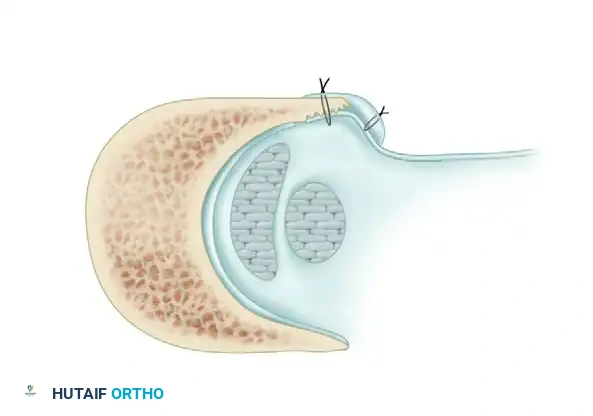

Axial cross-section demonstrating the deepened fibular groove. The peroneus brevis and longus tendons are reduced. Note the superior peroneal retinaculum being drawn tightly against the fibula using the pants-over-vest suture repair, eliminating the lateral false pouch.